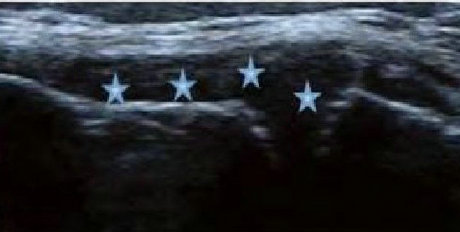

2、清晰显示滑膜异常形态,定量评估RA炎性

类风湿性关节炎以滑膜炎为基本病理改变,超声可观测到关节暗区的范围及厚度,判断有无滑膜增厚、显示不同程度的滑膜均匀或不均匀增厚,分辨滑膜呈绒毛状、团状或结节状结构向关节腔突起的形态。通过对滑膜厚度、水肿、炎性细胞浸润状况的分级、定量评估RA关节内滑膜的炎性程度。

Ⅰ级滑膜增生

轻度滑膜增生,不超过骨面 点连线

Ⅱ级滑膜增生

滑膜增生超过骨面 点连线,呈绒毛状,但不越过骨干

Ⅲ级滑膜增生

滑膜增生超过骨面 点连线,呈团块状延伸超过一侧骨干